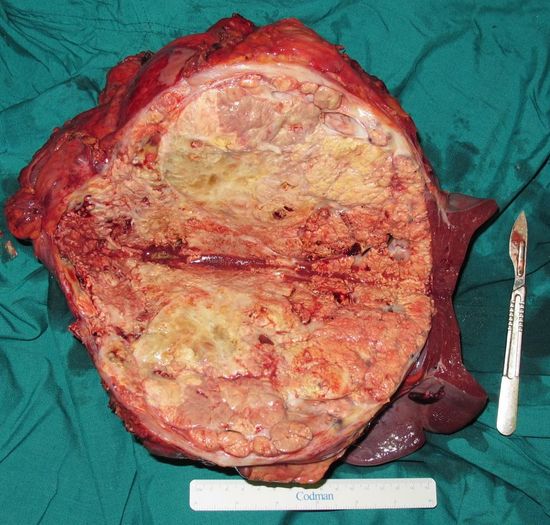

Удаленный опухолевый конгломерат